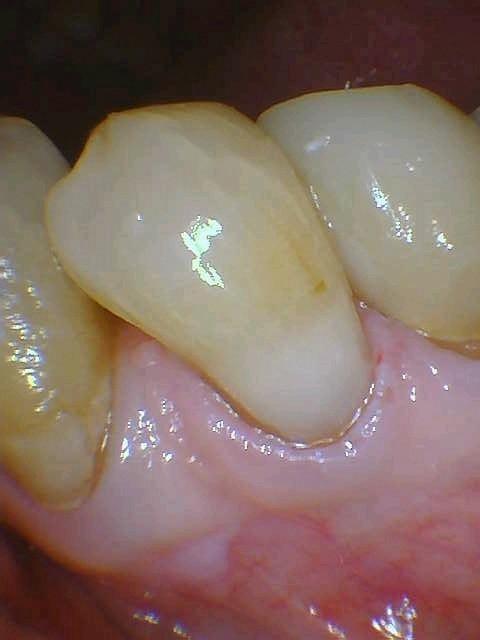

Bonded Composite Restoration

A new bonded composite restoration to replace a pre-existing, failing restoration

Before

After